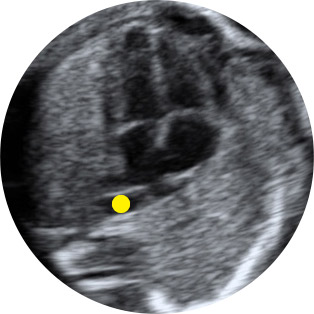

Οι νεφροί και τα επινεφρίδια βρίσκονται κάτω από το επίπεδο του στομάχου σε κάθε πλευρά μπροστά από την ΣΣ και φαίνονται από την 9η εβδ., αλλά σε όλες τις περιπτώσεις από την 12η εβδ. Η ηχογένειά τους είναι μεγάλη στις 9εβδ., αλλά ελαττώνεται με την ηλικία κύησης. Οι επιμήκεις και οι εγκάρσιες τομές της κοιλιάς εξετάζουν τους νεφρούς. Πιο συγκεκριμένα, στην επιμήκη τομή έχουν ελλειπτική εικόνα, ενώ στην εγκάρσια ωοειδή. Είναι λίγο πιο υποηχοϊκοί σε σχέση με το ήπαρ και τις έλικες του εντέρου. Στις 20 εβδ. έχουν μια υπερηχοϊκή περιοχή σαν κάψουλα, με τη φλοιώδη μοίρα πιο ηχογενή από τη μυελώδη. Με την πρόοδο της ηλικίας συσσωρεύεται λίπος γύρω από τους ιστούς, αυξάνοντας τα όρια και κάνοντάς τους πιο διακριτούς από τα γύρω όργανα. Στις 26-28 εβδ. μπορούν να φανούν οι νεφρικοί κάλυκες και οι τοξοειδείς αρτηρίες. Το μήκος και η περίμετρος των νεφρών αυξάνει με την ηλικία, αλλά ο λόγος της περιμέτρου του νεφρού προς αυτή της κοιλιάς παραμένει σταθερός, ίσος με 30% σε όλη την κύηση περίπου. Η προσθοπίσθια διάμετρος του νεφρού είναι <5mm 15-19wk., <6mm 20-29wk. <8mm30-40wk. Οι φυσιολογικοί ουρητήρες σπάνια φαίνονται σε απουσία περιφερικής απόφραξης ή παλινδρόμησης. Η ουροδόχος κύστη φαίνεται από την 11εβδ. στο 80% και άνω του 90% στην 13εβδ.